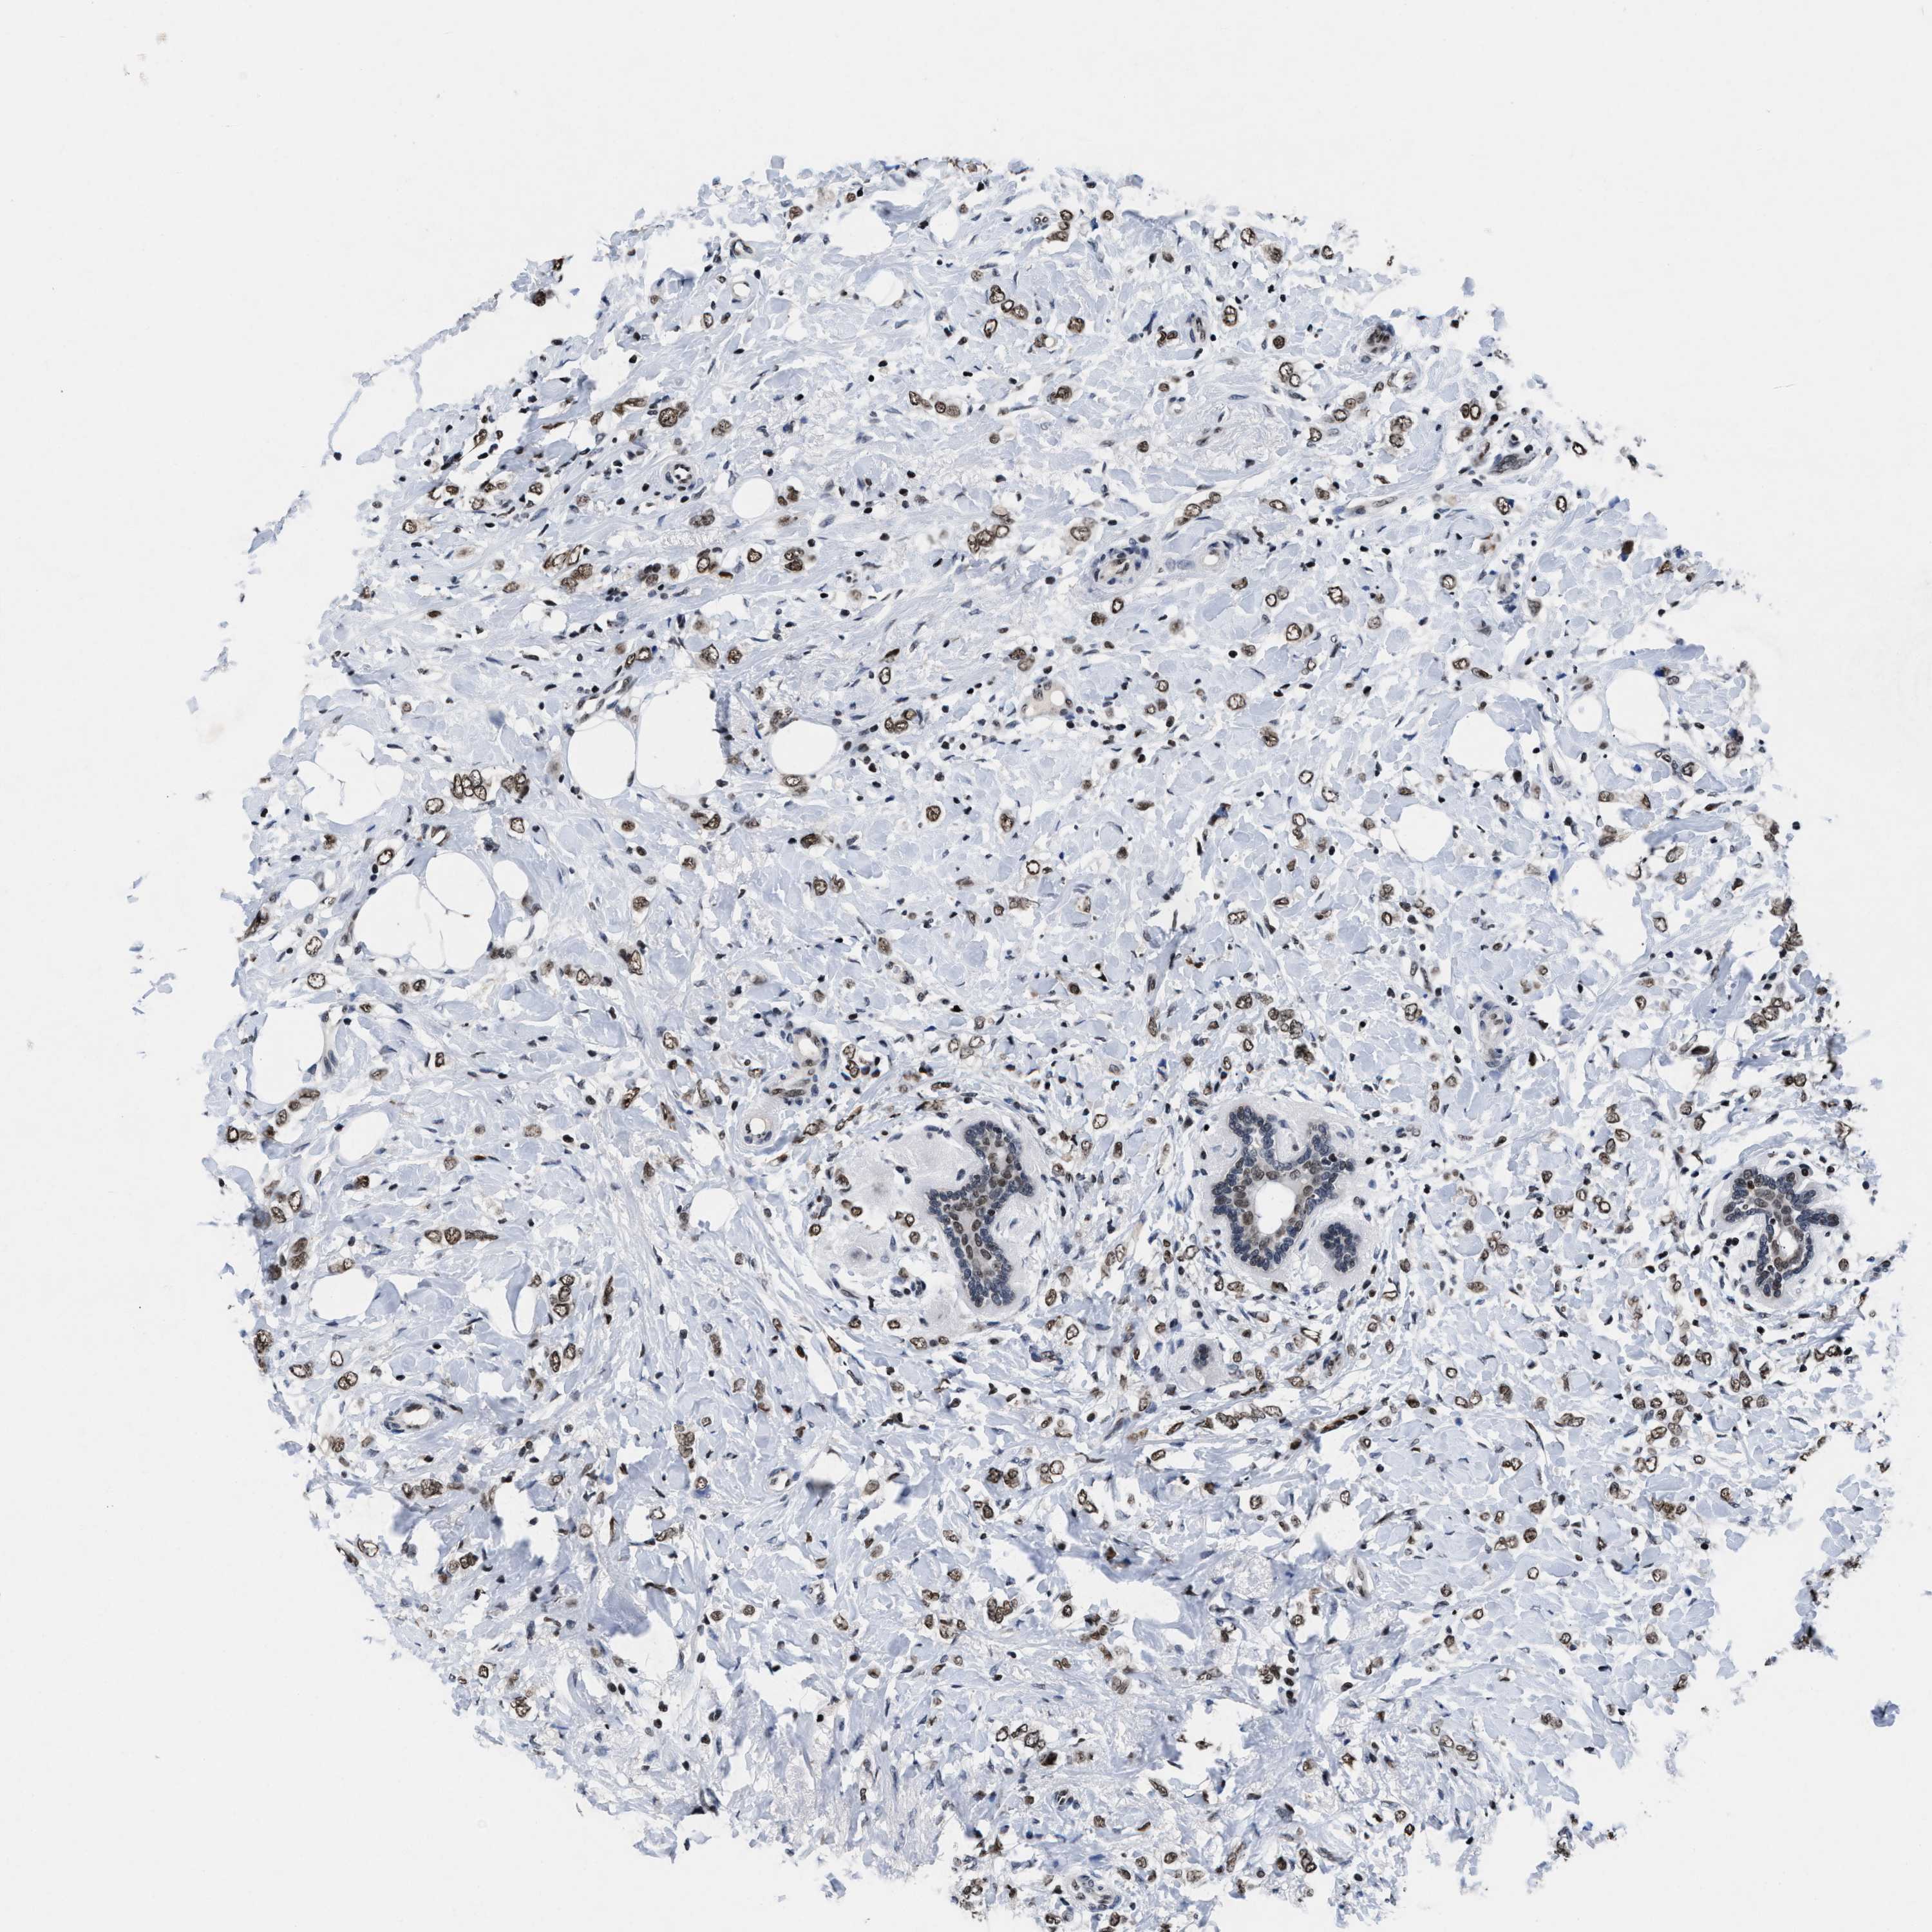

BRCA TCGA BRCA VALIDATION PROTEIN EXPRESSION